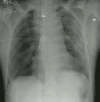

The patient presented to the emergency room following a high speed motor vehicle accident.

The initial portable CXR demonstrated multiple left sided rib fractures, widening of

the mediastinum with loss of the aortic contour, a left apical pleural cap, deviation of

the NG tube to the right, and widening of the right paraspinal line.